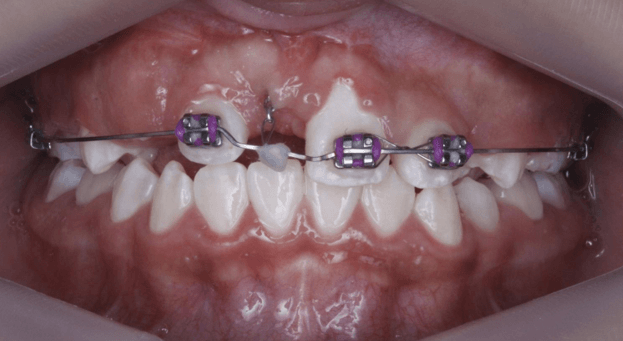

En los siguientes controles se observa la corona del incisivo central 1.1 en boca con giroversión hacia mesial, desde este punto, el objetivo es colocar al incisivo dentro del arco dental. En el primer control post erupción se realiza el escaneo intraoral posterior a la colocación del bracket para 1.1 y un botón lingual (Fig. 24), estos permitirán realizar un movimiento de cupla con el objetivo de corregir la giroversión del mismo. Para continuar con el posicionamiento del incisivo, en el siguiente control se realizó la técnica de doble arco utilizando un 0.012 niti sujetado a los incisivos 1.2, 1.1, 2.1 y 2.2 junto con un arco 0.18 acero con un doblez de extrusión para el incisivo 1.1. (Fig 25)

Fig 24 y 25. Fotografía escaneo intraoral junto a técnica de doble arco con doblez de extrusión.

Después de colocar el incisivo 1.1 en el arco dental, para su alineación, se retiró el botón lingual, se colocó el arco 0.18 niti termoactivado (Fig 26) y se terminó el caso con un arco 17x25 niti termoactivado para permitir la correcta colocación de la raíz dentro del hueso alveolar.

Fig 26. Fotografía de arco 0.018 niti para alineación dental